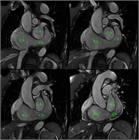

心室中隔欠損症(Ventricular Septal Defect, VSD)

1. 成人循環器内科医が診るVSDのほとんどは小欠損孔のrestrictive VSDとなる。なかにはsmall-moderate size(小~中欠損孔)restrictive VSDで小児期には血行動態的に影響がなかったが、成人期に心室コンプライアンス低下や体血管抵抗の上昇により左→右シャントが増加して左室拡大をきたすことがある。

1. 必要な検査と所見:身体所見、心エコー

1. 大動脈弁閉鎖不全症、肺高血圧合併例は専門施設への紹介を検討する。